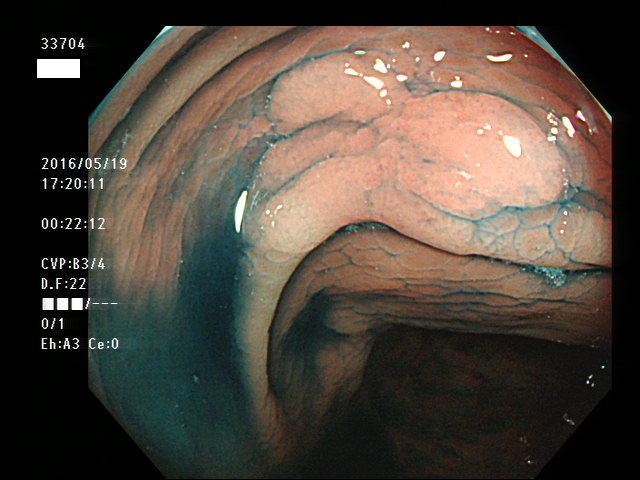

上記100名より抽出した平坦・陥凹型腺腫(=癌化の危険が高いが見落としやすい病変)の内視鏡写真